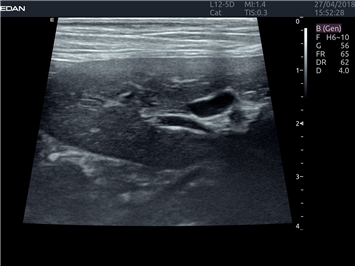

EDAN Acclarix LX4 VET

EDAN Acclarix LX4 VET представляет собой профессиональную ультразвуковую систему, специально разработанную для ветеринарных исследований. Сочетание стабильности, высокой производительности и эффективности делает эту систему идеальным выбором для современной ветеринарной практики.